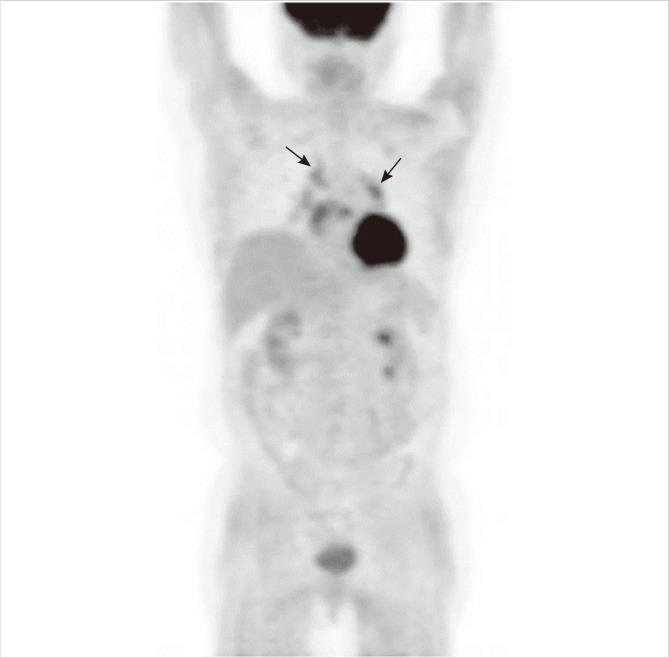

Fig. 1.

F-18 FDG PET/CT findings. In maximum intensity projection (MIP) (A) and coronal (B, C) images of PET/CT, increased uptake was noted in mediastinal and bilateral hilar lymph nodes (arrows). In addition, multiple streaky and dotted muscular uptakes were noted along whole body. Nodular uptake was seen in left lower lateral leg (arrowhead) in MIP (A) and transaxial (D) images, and excisional biopsy was performed in this mass.

In November 2009, a 50-yr-old female was admitted to our hospital with idiopathic transient pulmonary edema. Her weight was 49 kg, creatinine clearance 33.8 mL/min and calcium 9.9 mg/dL. Her echocardiogram showed mild diastolic dysfunction with ejection fraction of 55%. Her pulmonary function was moderately restricted with 51% of forced vital capacity. Her pulmonary edema was rapidly improved with diuretics therapy. In August 2010, she was re-admitted with hypercalcemia. She had underlying diabetes for 20 yr. Her diabetes was complicated with proliferative retinopathy, chronic renal impairment, and a chronic foot ulcer. At the time of her recent admission, her weight was 37 kg and she appeared chronically ill and emaciated. She reported 2 weeks of general weakness. We could not find any abnormal mass or tenderness except generalized muscle atrophy at the beginning. Creatinine clearance was 19.4 mL/min, calcium 14.5 mg/dL, phosphate 5.0 mg/dL, and ionized calcium 1.78 mM/L. Her 24-hr urine calcium level was 186.2 mg/day, and intact parathyroid hormone (PTH) of 15.77 pg/mL. These ambiguous laboratory findings prompted further studies of non-parathyroid-related hypercalcemia. Her 25-hydroxy Vitamin D level was 21.3 ng/mL, 1,25-dihydroxy Vitamin D was 43.1 pg/mL (normal, 25.1-66.1), and parathyroid hormone related peptide (PTHrP) was under 1.1 pM/L. The thyroid hormone level, serum electrophoresis and tumor markers were normal. The angiotensin-converting enzyme (ACE) level was elevated to 353.1 IU/L (normal, 20-70), and muscle enzymes (CPK/LDH/AST) were normal. The chest radiograph, neck ultrasound, and whole body bone scan were unremarkable. F-18 FDG PET/CT was performed for the evaluation of possible hidden malignancy. The PET/CT showed increased uptake of small lymph nodes in the subcarina and both hila. In addition, multiple streaky and dotted muscular uptakes were noted along whole body including the back and extremities (Fig. 1). We reexamined her whole body and found a 2 cm-sized soft and non-tender mass in the left gastrocnemius muscle. Excisional biopsy was performed of the mass, and the microscopic finding demonstrated non-necrotizing granulomas with multinucleated giant cells and without acid-fast bacilli or fungi (Fig. 2) consistent with muscular sarcoidosis. Imaging studies also revealed gallstones and bilateral renal stones, and we performed extracorporeal shock wave lithotripsy of the ureteral stone successfully. However, some renal stones remained.